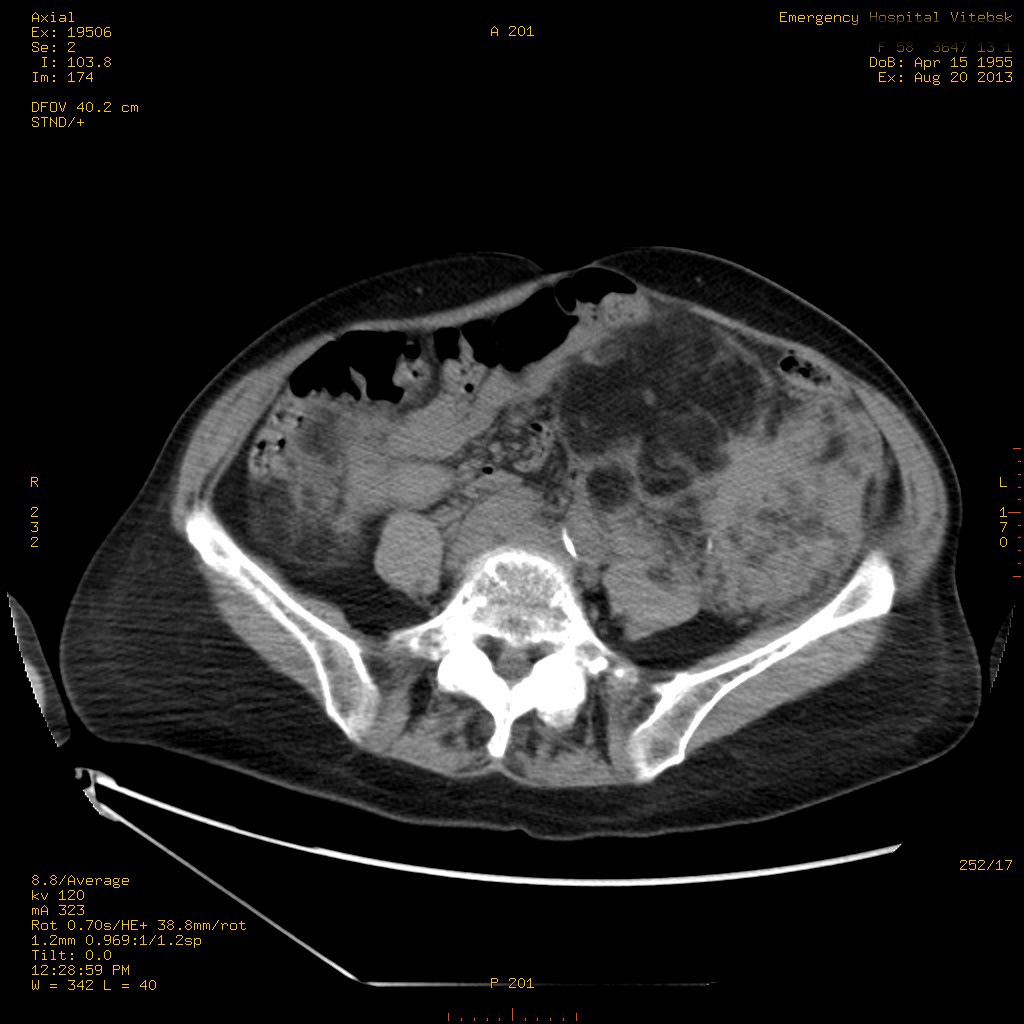

Пожилая женщина с нормальными мочевиной и креатинином.

Ангиомиолипоматоз почек , думаю компонент туберозного склероза.

Да, туберозный склероз.

Случай консультирован на кафедре радиологии Католического университета г.Лёвен (Бельгия) - зав каф. профессор Р.Оуен.